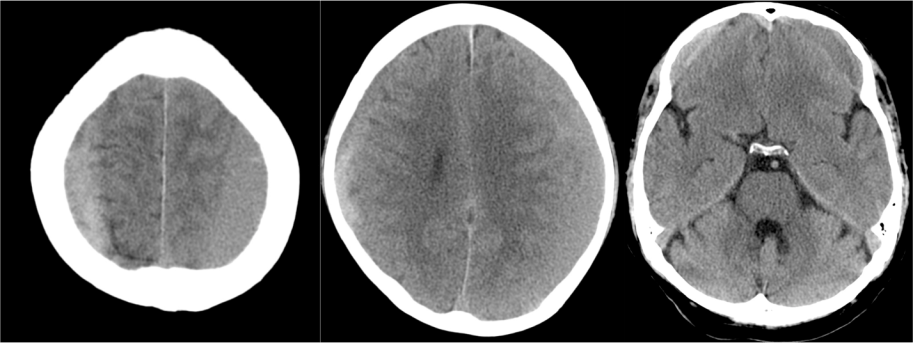

1- Edema cerebral difuso: Aparece en las primeras 48 horas del traumatismo. Se identifica por:

- Produce efecto de masa.

- Borramiento de surcos = pérdida de la interfase sustancia gris-sustancia blanca.

- Otros: signo del cerebelo blanco, falsa hemorragia subaracnoidea…